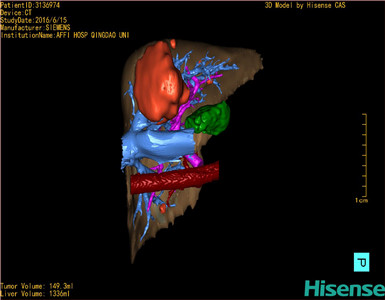

将0.625mm双源薄层CT资料的静脉期和动脉期Dicom格式文件导入海信CAS系统。

通过调节窗宽窗位调整CT序号,对肿瘤,肝实质,胆囊,下腔静脉,肿瘤,肝动脉、门静脉及肝静脉等进行三维重建;系统自动计算肿瘤体积和肝脏体积。

模拟手术操作,自动计算切除肿瘤体积。肝脏体积为1336ml,肿瘤体积为149.3ml,肿瘤体积为肝脏体积的11.2%,通过比对50-60岁正常肝脏体积为1330.41±329.13 ml,通过术前模拟手术,精准判断切除后剩余肝脏体积能耐受,避免肝衰竭发生。

术前手术方案的规划。

术前三维重建:重建图片